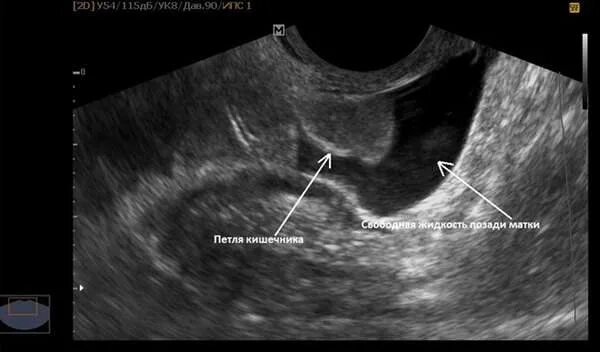

Позадиматочное пространство